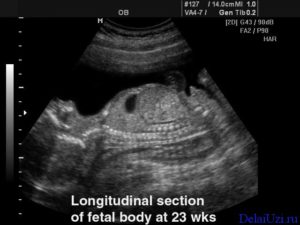

На УЗИ отчетливо виден малыш. Он шевелит ручками и ножками, иногда поворачивает лицо к аппарату. Так родители могут увидеть контуры личика. Обследование покажет, какую позицию он занимает и размеры плода.

Хорошо просматривается мозг ребенка, некоторые органы и, конечно, его сердечко. Оно уже довольно сильное, качает весь объем крови. На этом сроке беременности матери нужно есть достаточно мяса: оно помогает в развитии системы кровообращения.

Начиная с 23 недели, нормы роста для каждого ребенка становятся уже индивидуальными, и специалист при проведении УЗИ более всего обращает внимание на развитие и активность внутренних органов.

В частности фиксируется активность головного мозга, особенное внимание уделяется расширению желудочков мозга, что может означать гидроцефалию.

Частоте сердцебиения также уделяется не малая роль, в норме у малыша на сроке беременности в 23 недели должно осуществляться не менее 160 ударов в минуту.